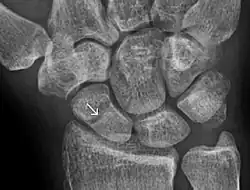

![]() | |

| An X-ray showing a fracture through the waist of the scaphoid | |